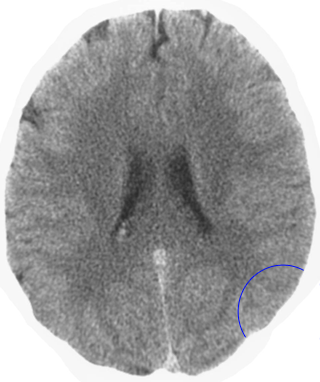

Which is the brain relais that is shown here? 25 Questions each cycle, try more!

Question 1 of 25

Middle ear mucosa left

Rectal mucosa

Coronary arteries, aortic arch, carotid arteries, bradycardia, penile sensitivity, clitoral sensitivity

Liver

Left hemispheres of the retinas

Lesser curvature of the stomach, mucosa of the bile ducts, pancreatic ducts, bulb of the duodenum